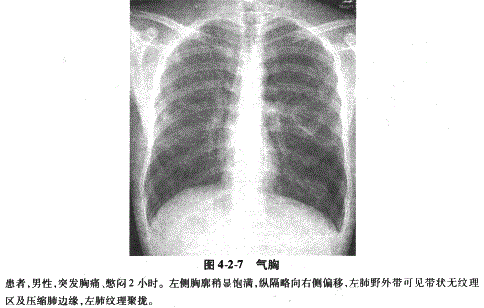

空气进入胸腔则形成气胸。X线表现为肺向肺门方向压缩,其与胸壁间出现透明含气区,其内无肺纹理,气体较多时纵隔向健侧移位,患侧膈下降,肋间隙增宽(图4-2-7)。合并胸腔积液时立位片出现横贯胸腔的液平面,液面上方为空气及压缩肺组织,称为液气胸(图4-2-8)。如脏层、壁层胸膜发生粘连,可形成局限性或多房性气胸或液气胸。